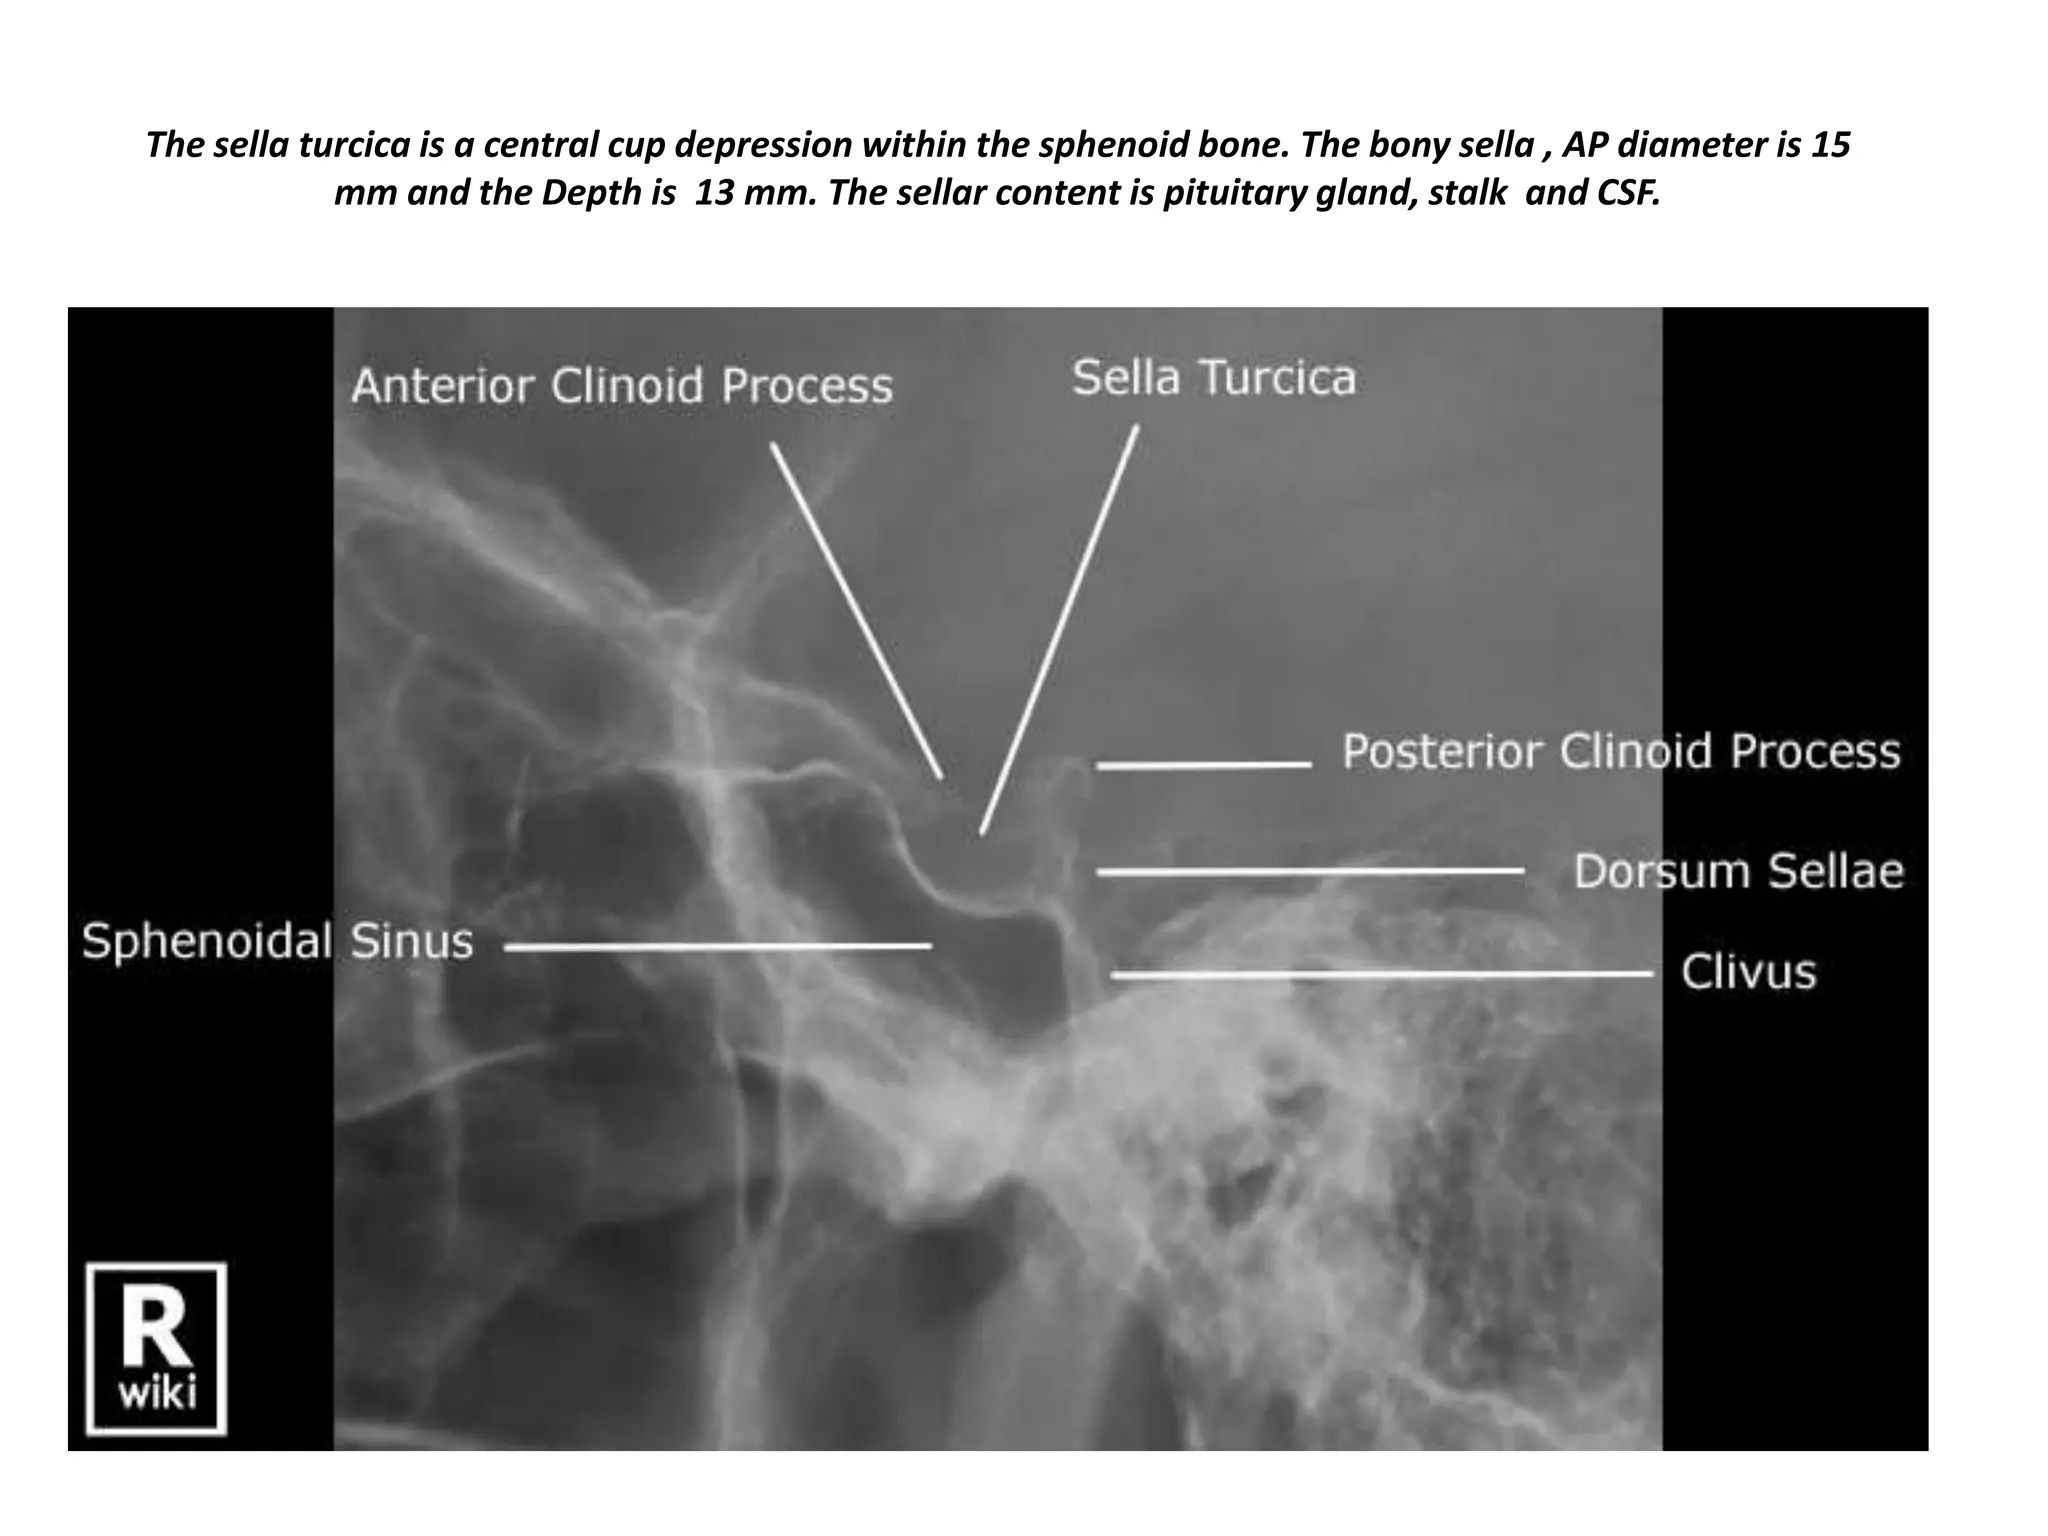

The sella turcica is a central cup depression within the sphenoid bone. The bony sella , AP diameter is 15

mm and the Depth is 13 mm. The sellar content is pituitary gland, stalk and CSF.